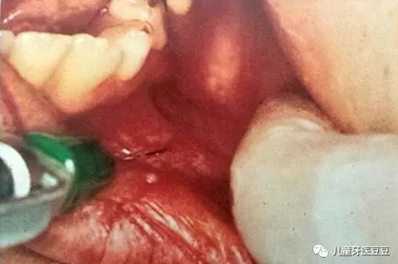

0IG~(~2ELPN~$0HI(Q[)2$6.png

乳牙反復(fù)根尖發(fā)炎導(dǎo)致繼承恒牙發(fā)育不良